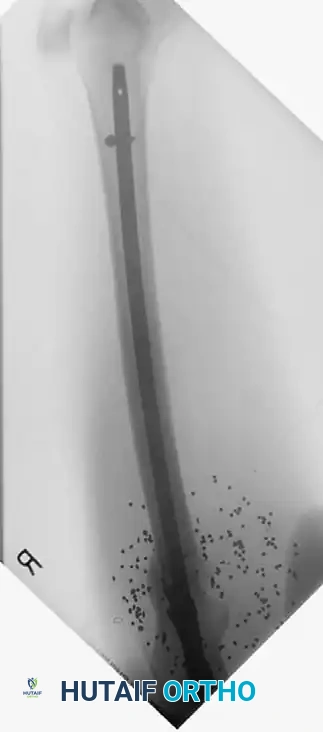

POSTOPERATIVE PROTOCOLS AND CONVERSION TO DEFINITIVE FIXATION

The goal of DCO is to bridge the patient through the acute physiological crisis. Once the patient's lactate has cleared, coagulopathy is reversed, and inflammatory markers have peaked and begun to trend downward (typically between days 5 and 10), the patient is optimized for conversion to definitive fixation.

Lerner et al. noted complications of pin track infection with emergency external fixation; however, Harwood et al. demonstrated that there is no significant increase in deep infection rates if the conversion from external fixation to intramedullary nailing is performed in a timely manner—defined strictly as within 14 days of the initial injury.

If pin sites show signs of superficial infection (erythema, purulent discharge), the external fixator should be removed, the pin tracts aggressively debrided and over-reamed, and the patient placed in skeletal traction or a cast until the soft tissues sterilize, prior to definitive internal fixation.

Long-Term Functional Outcomes

The ultimate functional recovery of the polytrauma patient depends heavily on the initial decisions made in the trauma bay. Early stabilization of the spine, pelvis, and major articular fractures decreases the sequelae of forced recumbency (DVT, decubitus ulcers, pneumonia).